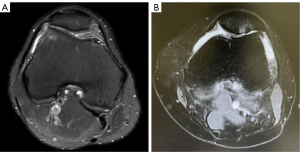

Our inclusion criteria for receiving OWHTO were (I) isolated medial compartmental OA or osteonecrosis of the medial femoral condyle, which included patients with a varus malalignment of the leg and persistent pain in spite of having undergone conservative treatment for more than 3 months; (II) active compliance with our postoperative rehabilitation program; and (III) a range of motion of more than 120° flexion. The indications for LRR were as follows: (I) preoperative significant anterior knee pain; (II) patellofemoral OA, Kellgren-Lawrence (KL) classification ≥ grade II; (III) patellofemoral cartilage damage visible on arthroscopy, International Association of Cartilage Repair Association (ICRS) grade 3 or 4; and (IV) evidence of lateral patellar compression syndrome on magnetic resonance imaging (MRI) (Figure 1). The exclusion criteria were as follows: (I) a follow-up duration of less than half a year; (II) incomplete imaging data; (III) joint infection; (IV) rheumatoid arthritis; (V) complication with lateral compartment OA; (VI) flexion contracture >15°; (VII) descending osteotomy; and (VIII) medial patellar tilt and shift on preoperative imaging or arthroscopy.